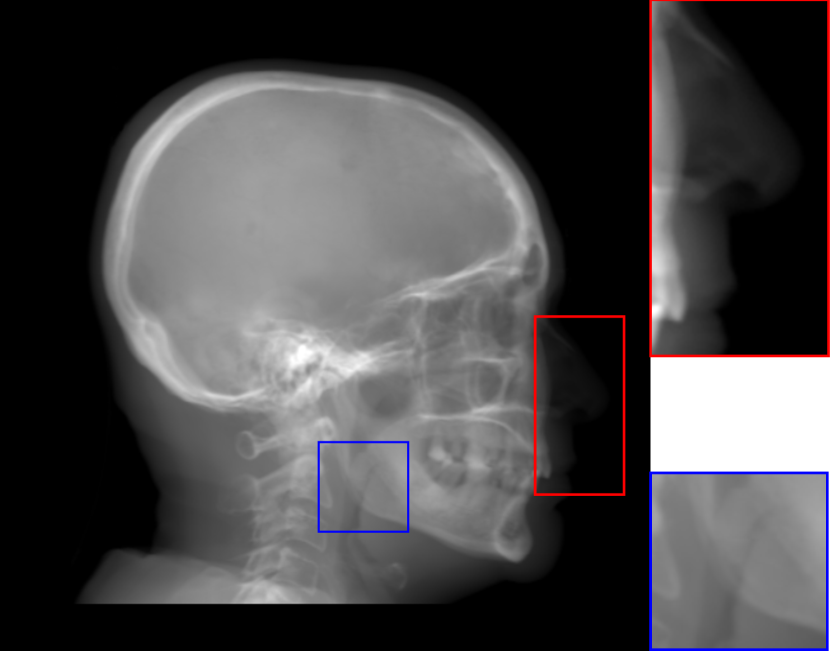

Refer to caption

(a) Orthogonal RayCast, 8.32

(b) Perspective RayCast, 8.23

(c) MIP100, 7.59

(d) CycleGAN, 5.53

(e) Orthogonal RayCast, enhanced, 7.78

(f) Original sigmoid transform, 6.93

(g) Proposed, 6.83

(h) Proposed with perspective projection, 6.77

Fig. 8: Synthetic cephalogram examples from 3D CBCT volumes with different methods. (a)-(d) are comparison results while (e)-(h) are the (intermediate) results of our proposed method: (a) RayCast using orthogonal projection; (b) RayCast using perspective projection; (c) MIP using the largest 100 pixels along each orthogonal ray; (d) CycleGAN using patches from (a) and ISBI real conventional cephalograms; (e) RayCast using orthogonal projection from the skeleton enhanced volume; (f) original sigmoid transform of (e) using Eqn. (4) with air background recovery; (g) modified sigmoid transform of (e) using Eqn. (6), the final Type I synthetic cephalogram using orthogonal projection; (h) the final Type I synthetic cephalogram using perspective projection. The nose ROIs are redisplayed in the intensity window [0, 125] for better visualization. The mandible angle ROIs are for the visualization of the difference between orthogonal projection and perspective projection. The perceptual index of each synthetic cephalogram is displayed in the corresponding subcaption.

The synthetic cephalograms generated by different methods are displayed in Fig. 8. Figs. 8(a) and (b) show the cephalograms synthesized by the orthogonal [33] and perspective [21] RayCast methods, respectively, which are the most widely used methods for cephalogram synthesis from CBCT volumes. Comparing Fig. 8(b) to Fig. 8(a), due to different magnification factors of structures at different positions in perspective projection, anatomical structures on both sides of the midsaggital plane cannot overlap well, for example, the projections of the left and right mandible (gonial) angles in the zoom-in ROI in Fig. 8(b). In Figs. 8(a) and (b), the skeleton structures, soft tissues and airways are well observed. However, the image contrast in these two synthetic cephalograms are different from conventional cephalograms (Fig. 2(a)). The cephalogram synthesized by MIP using the largest 100 pixels along each orthogonal ray is displayed in Fig. 8(c). In this subfigure, skeleton structures are well observed since they have high intensity. Nevertheless, low intensity structures, e.g. the throat airway, might disappear. The CycleGAN [59] synthetic cephalogram is shown in Fig. 8(d). Compared with the conventional cephalogram example in Fig. 2(a), it has the closest image contrast. Hence, it achieves the best perceptual index of 5.53. However, some detailed anatomical structures are incorrect. For example, the nose has extremely low intensity in the zoom-in ROI. It also suffers from geometric distortion. As a consequence, the stitching artifacts are visible.

Figure 8(e)-(g) are the Type I synthetic cephalograms of different steps using orthogonal projection. Fig. 8(e) is the orthogonal RayCast celphalogram synthesized from the enhanced CBCT volume using Eqn. (1). Compared with Fig. 8(a), skeleton structures in Fig. 8(e) have higher contrast. Fig. 8(f) is obtained by applying the original sigmoid transform in Eqn. (4) to Fig. 8(e), where the skeleton structures are further enhanced. Moreover, the appearance of Fig. 8(f) is very close to conventional cephalograms. However, the soft tissues like the nose and lips have an almost constant intensity value, as displayed in the zoom-in ROI in Fig 8(f). The final Type I synthetic cephalogram with orthogonal projection is displayed in Fig. 8(g). With the proposed modified sigmoid transform in Eqn. (6), the contrast in the soft tissues is brought back, as displayed in the zoom-in ROI. For comparison, the final Type I synthetic cephalogram with perspective projection is displayed in Fig. 8(h). Compared with Fig. 8(g), the mandible angles in the zoom-in ROI of Fig. 8(h) are not overlapped well due to perspective magnification.